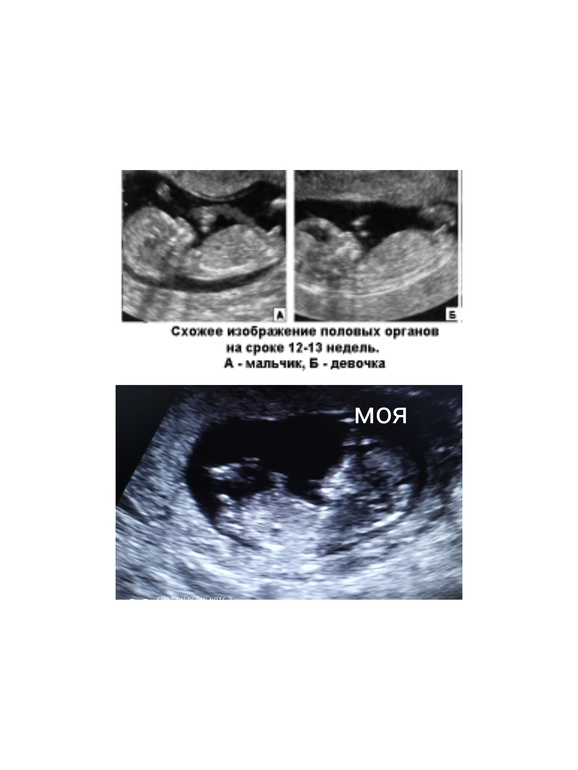

У нас была такая история, муж хотел узнать при родах кто у нас получился 😀 я же не готова была ждать так долго и решили мы в феврале пойти на 3Д УЗИ.